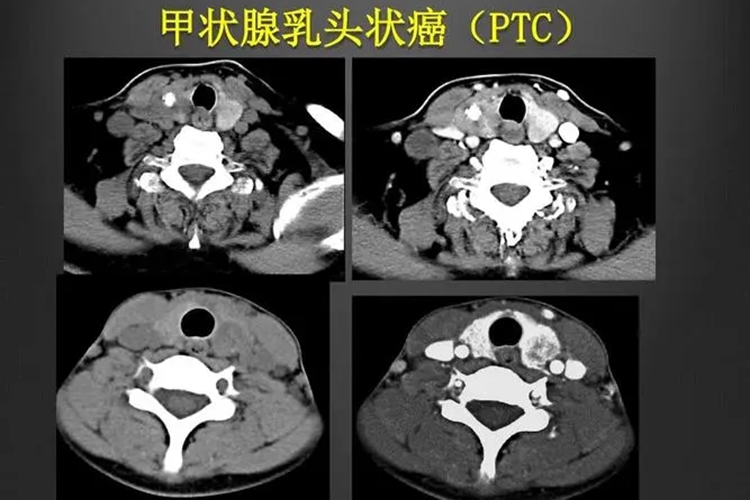

甲状腺乳头状癌表现为无痛性的颈部结节和甲状腺结节,可伴有呼吸困难等症状,其发病与放射线辐射、碘摄入过量或不足等因素有关。

甲状腺乳头状癌是甲状腺癌最常见的病理类型,大多发生于20-50岁的成年人,多与体检时发现或患者触及颈部肿块而就诊。临床上体格检查可触及甲状腺结节及局部淋巴增大,其他表现极少,有时癌瘤小时,位于甲状腺深部而不能触及。

影响检查可见低回声实质结节,可伴区域囊性变,也可为囊性结节内伴乳头状实质突起。同时还可有细小钙化,对应为甲状腺乳头状癌组织中的沙砾体,是甲状腺乳头状癌的典型超声表现。